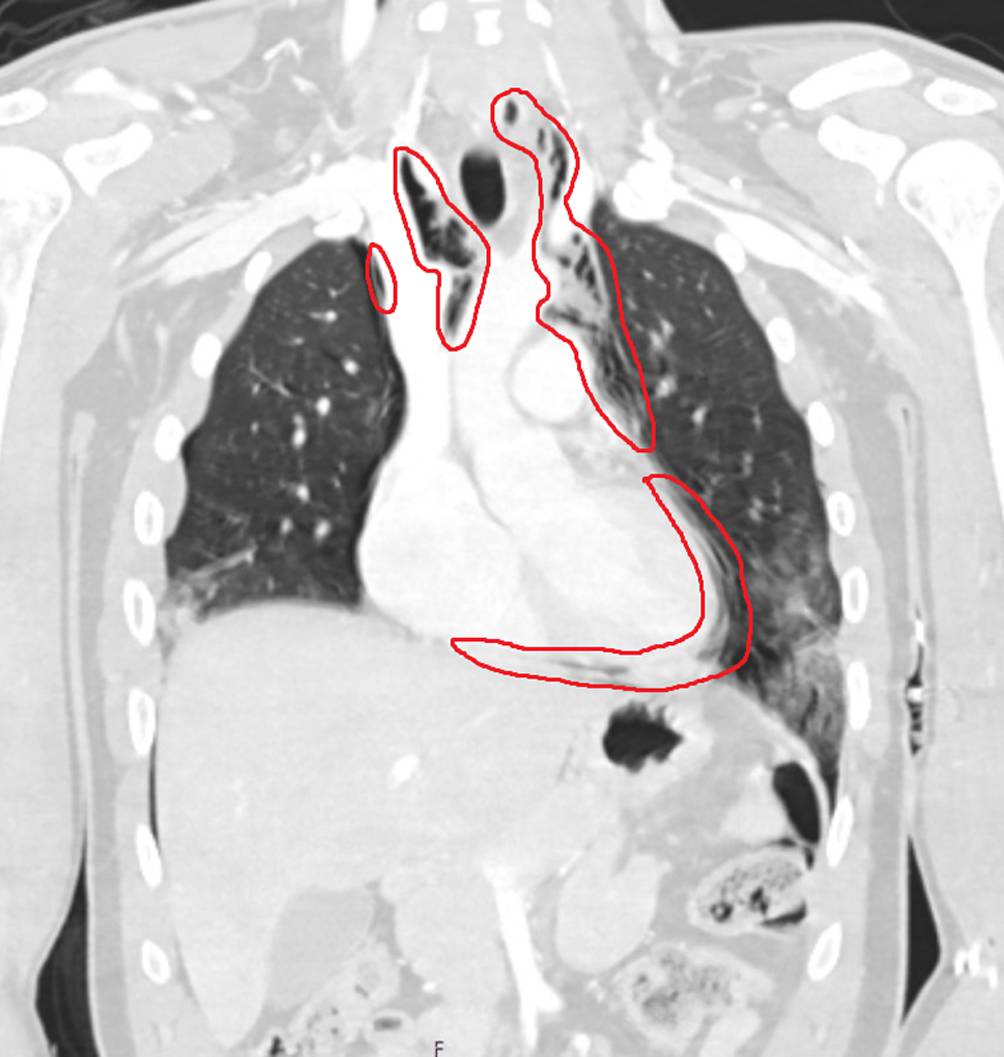

Abb. 4

Koronarschnitt der Computertomographie im Rahmen der Schockraumversorgung mit Nachweis der tracheobronchialen Verletzung (Kreis)

Aufgrund des nachgewiesenen Pneumomediastinums wurde unmittelbar nach Abschluss der CT-Diagnostik noch im Schockraum eine Bronchoskopie durchgeführt. Dabei zeigte sich dorsal auf Höhe der Carina eine etwa 3 cm lange Trachealruptur, die sich spiralförmig bis in den rechten Hauptbronchus erstreckte (Abb. 3). Die Tubusspitze lag 5,5 cm kranial von der Carina. Die nun bronchoskopisch diagnostizierte tracheobronchiale Ruptur ließ sich retrospektiv auch in den CT-Bildern verifizieren (Abb. 4). Somit bestand die dringende Op.-Indikation zur Übernähung der Trachea über eine rechtsseitige Thorakotomie. Noch im Schockraum vor Verlegung in den OP wurde linksseitig eine Thoraxdrainage in Bülau-Position eingelegt, bei unmittelbar folgender Thorakotomie rechts und aktuell tolerierbarer kardiopulmonaler Situation verzichteten wir zunächst auf eine Drainage-Anlage rechts. Durch die Kollegen der Gastroenterologie wurde noch vor Verlegung in den OP endoskopisch eine Begleitverletzung des Ösophagus ausgeschlossen. Auf eine präoperative magnetresonanztomographische Darstellung (MRI) der spinalen Achse bei bis dahin nicht erklärter peripherer Plegie der Beine und des rechten Arms wurde aufgrund der zeitdringlichen thoraxchirurgischen Op.-Indikation verzichtet.